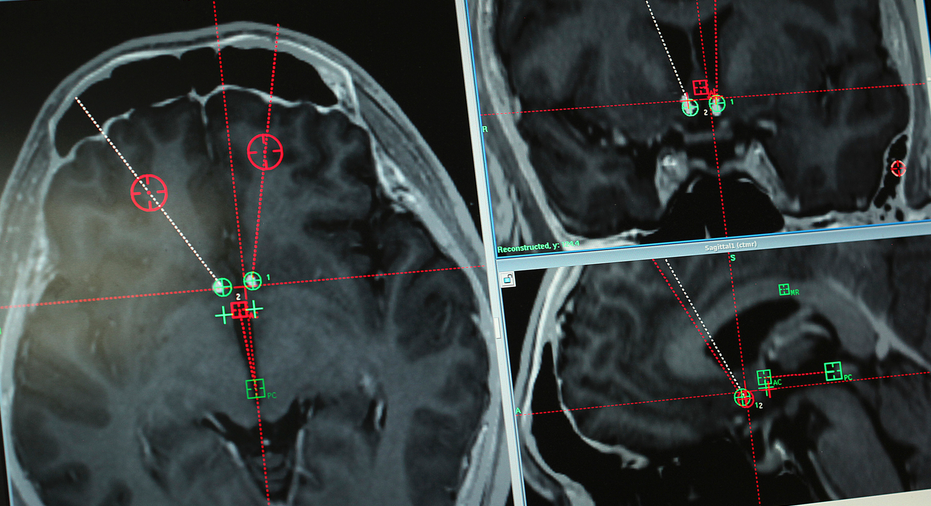

This Monday, Oct. 29, 2018 photo shows a brain scan of a methamphetamine addict with the path of electrodes that doctors at Ruijin Hospital in Shanghai, China implanted to stimulate an area of the brain associated with addiction. Western attempts to push forward with human trials of deep brain stimulation for drug addiction have foundered, even as China has emerged as a hub for this kind of research. But the vast suffering wrought by the U.S. opioid epidemic may be changing the risk-reward calculus. Now, the experimental surgery for addiction is coming to America. (AP Photo/Erika Kinetz)

The treatment — deep brain stimulation — has long been used for movement disorders like Parkinson's. Now, the first clinical trial of DBS for methamphetamine addiction is being conducted at Shanghai's Ruijin Hospital, along with trials for opioid addiction. Yan is the study's first patient; for fear of losing his job, he asked that only his surname be published.

DBS builds on that history. The surgery involves implanting a device that acts as a kind of pacemaker for the brain, electrically stimulating targeted areas. Instead of irreversibly killing brain cells, the devices allow interventions that are — in theory — reversible. The technology has opened a fresh field of human experimentation globally.